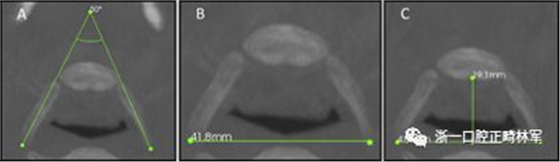

圖3.A,舌骨橫角; B,LL舌骨; C,AP舌骨。

圖4. A,下頜橫角; B,LL下頜骨; C,AP下頜骨。